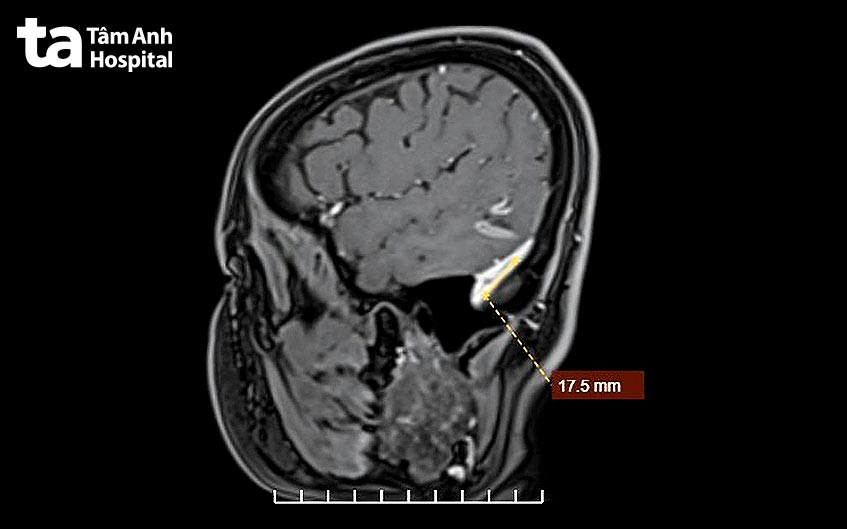

TS.BS Lê Văn Tuấn, Giám đốc Trung tâm khoa học Thần kinh cho biết, chị Lý có huyết khối tĩnh mạch não là một dạng đột quỵ hiếm gặp và chiếm 0,5% tổng số ca đột quỵ. Bệnh có tỷ lệ mắc là 0,22–1,32/100.000/năm. Bệnh có thể biểu hiện bằng các triệu chứng co giật, đau đầu, thường cơn đau nhiều, tăng dần. Bệnh nhân có thể có biểu hiện như các trường hợp đột quỵ khác là nói khó, liệt nửa người, liệt các dây thần kinh sọ. Một khi huyết khối được hình thành trong các xoang tĩnh mạch não hoặc các tĩnh mạch não thì nguy cơ huyết khối tiếp tục lan rộng ra và các triệu chứng tiếp tục tiến triển thêm. Nặng hơn là tăng áp lực nội sọ, gây tụt não dẫn đến tử vong. Điều trị huyết khối tĩnh mạch não cần phải dùng thuốc chống đông để ngăn tình trạng huyết khối tiến triển hay tái phát. Thuốc này làm tăng nguy cơ chảy máu não hoặc chảy máu ở các cơ quan khác trong cơ thể như chảy máu trong u xơ tử cung của chị Lý.

Sau 4 tháng dùng thuốc ức chế, chị Lý được TS.BS Lê Văn Tuấn, Giám đốc Trung tâm khoa học Thần kinh đánh giá tình trạng bệnh huyết khối đã an toàn cho não và có thể thực hiện cuộc mổ can thiệp cắt tử cung. Chị được ngưng uống thuốc kháng đông trước 24 giờ mổ.